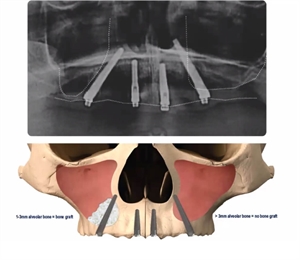

Trans-sinus implants x-ray

"Trans" means across or beyond. The implant is now placed in the newly formed bone. Since it traverses the area previously occupied by the sinus, it is called a trans sinus implant. Trans sinus implants unlike conventional implants can be placed directly in the implants. However, these implants are tilted at a certain angulation, such that the implant goes through the sinus and takes the support of the nasal (nose) bone. Dental surgeons usually recommend a bone grafting and sinus lift if the height of the bone is less than 3 mm. However, if the bone height is more than 3 mm, than these additional procedures can be avoided. Depending on this thickness, the surgeon also decides on the number of the implants that need to be placed.